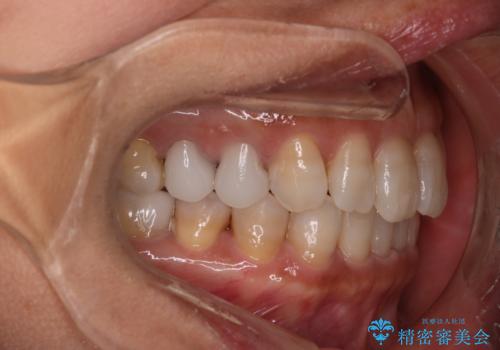

【インビザライン】下前歯だけを治したい

- 50代女性

- 矯正装置

- インビザライン

- 治療期間

- 8ヶ月

- 下前歯のがたつきにより唇を巻き込んでかんでしまい痛いため矯正をしたいという主訴で来院されました。今回は下顎前歯のみという強い希望があり、下顎のみのインビザライン矯正をしました。

叢生を改善するためのスペースはIPRと拡大を行いました。治療後は唇を巻き込んでしまう主訴が改善し、ご満足していただけました。